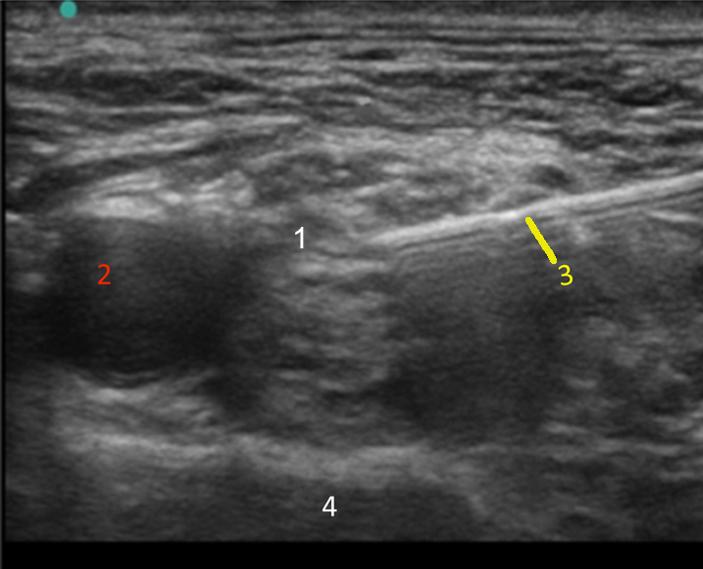

Supraclavicular Injection 2 Image

Brachial Plexus

Artery

Needle

Rib